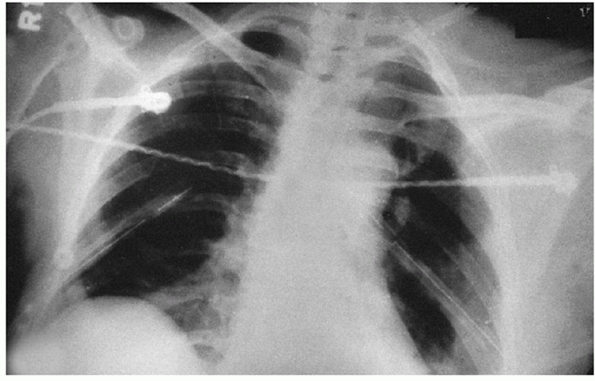

![]() |

|

FIGURE 39-15

Type VI AC dislocation. The distal end of the left clavicle is in the subcoracoid position. The high-energy trauma causing this injury is evidenced by the bilateral chest tubes in this patient. (From Rockwood CA, Young DC. Disorders of the acromioclavicular joint. In: Rockwood CA, Matsen F III, eds. The Shoulder. Philadelphia: WB Saunders, 1990:447. Courtesy of R.C. Erickson and D. Massillion.) |